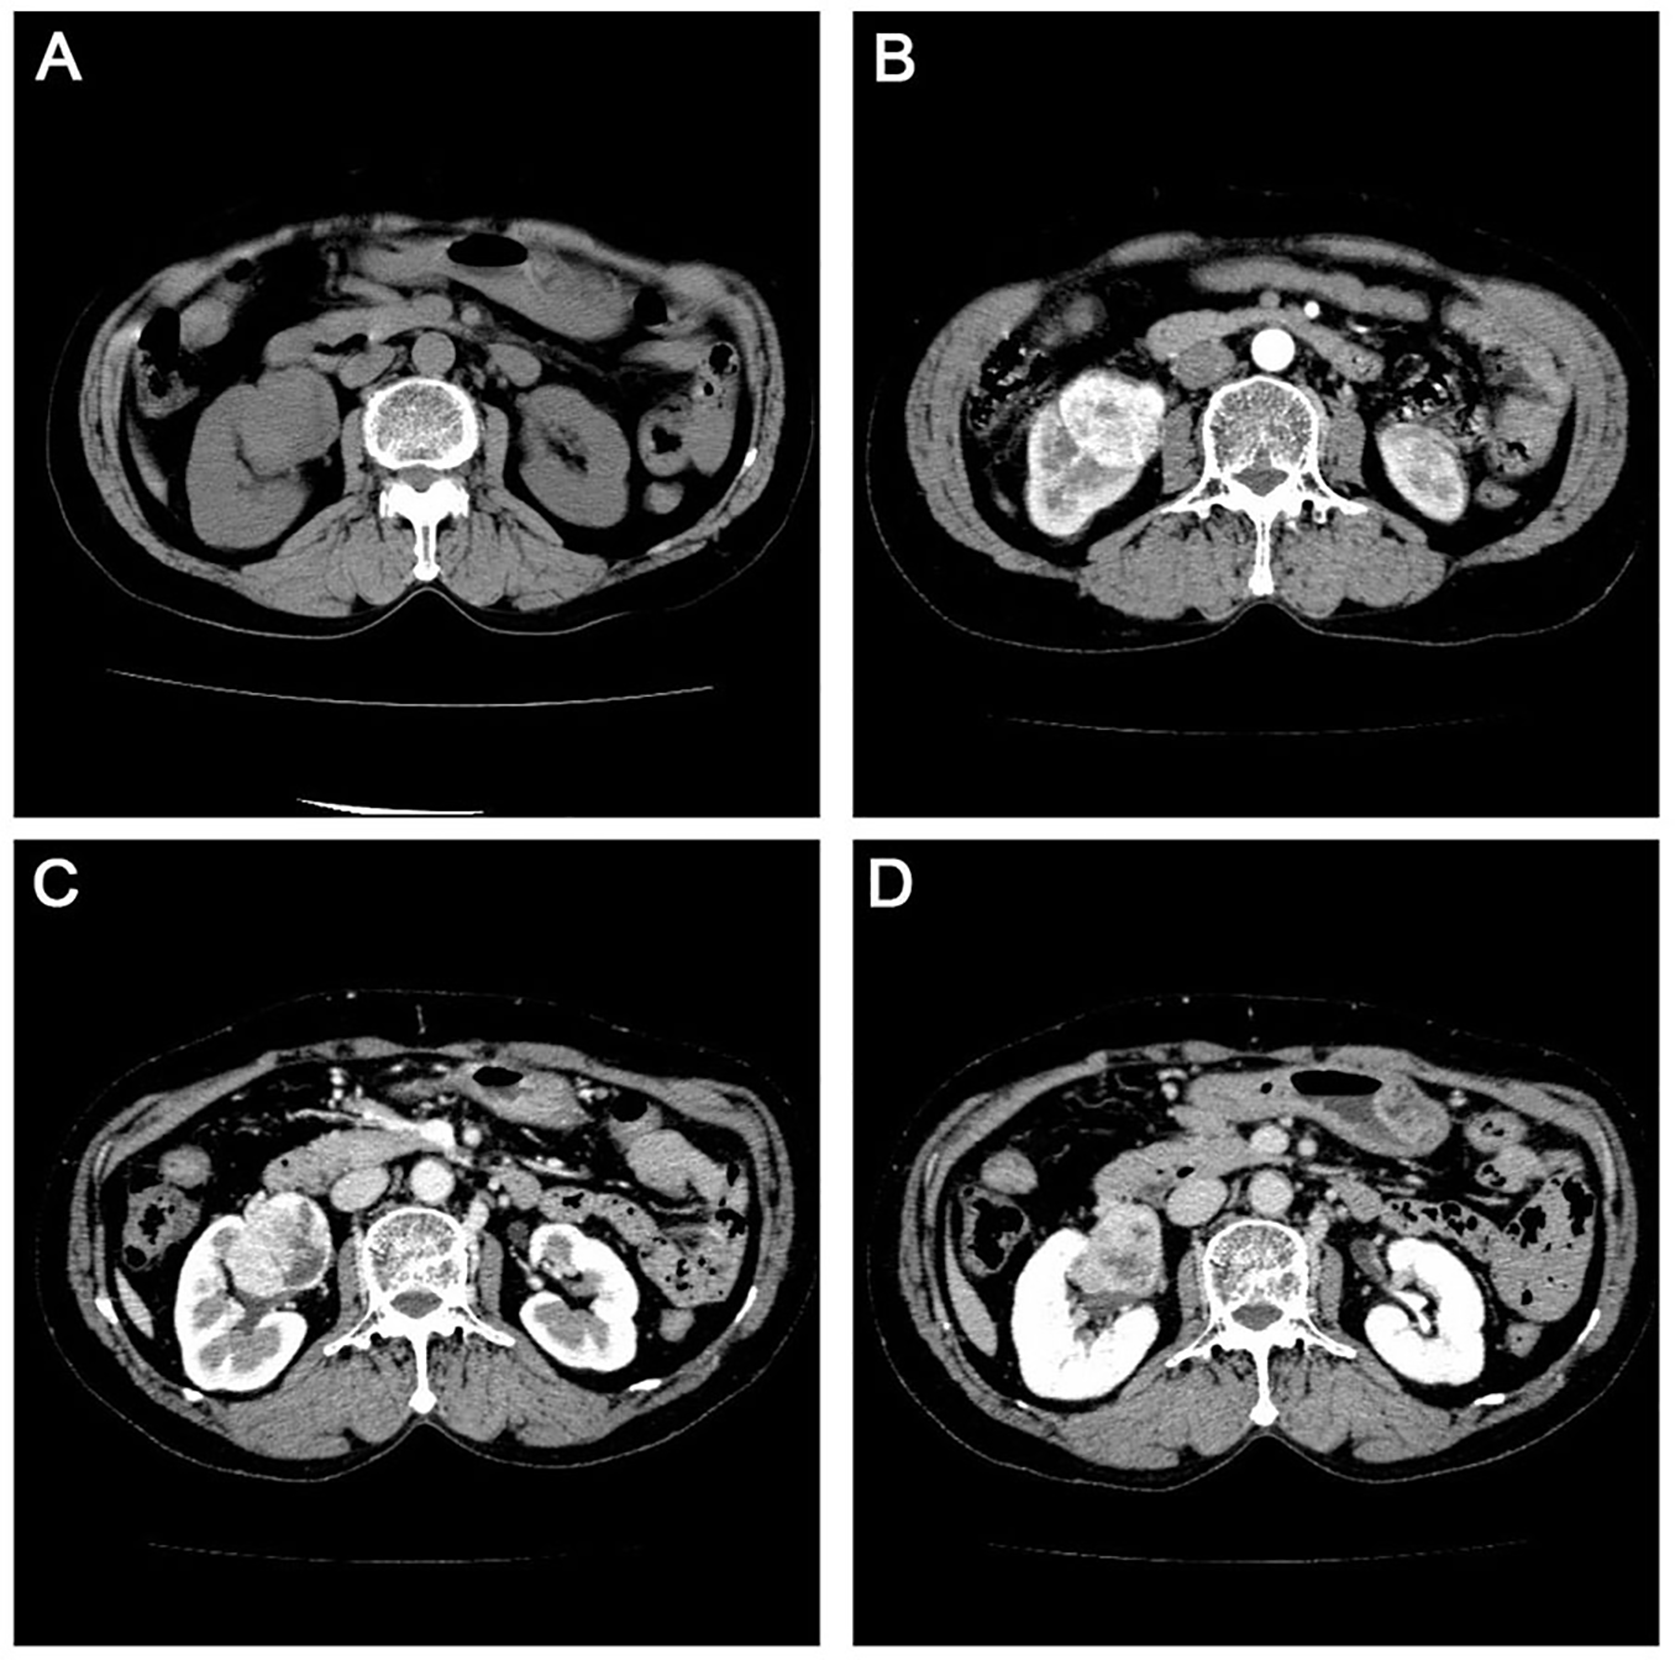

A 77-year-old female was referred to Dalian Friendship Hospital in October 2016 with discomfort at the waist as the main complaint. Urinary system ultrasound demonstrated a larger area mass measuring 7.1x6.2 cm in the upper pole of the right kidney. Abdominal computed tomography (CT) showed diffuse lesions of the right kidney without enlarged lymph nodes in the kidney or at other abdominal sites (Figure 1). Laboratory result of HCV, HBV, HIV, monoclonal component or autoimmune autoantibodies as follows: HBsAg 0.01 IU/ml (reference range 0.0-0.05 IU/ml); HBsAb 4.68 MIU/ml (reference range 0.0–10.0 MIU/ml); HBeAg 0.31 s/co (reference range 0.0–1.0 s/co); HBeAb 1.70 s/co (reference range > 1.0 s/co); HBcAb 3.31 s/co (reference range 0.0–10.0 s/co); HCV (-) 0.03 col (reference range <1 col); HIV (-); Antinuclear antibody (-); IgG of anti-double-stranded DNA antibody 12 IU/ml (reference range <24 IU/ml); Anti-neutrophil cytoplasmic antibody (-); Anti-cyclic cucurbita polypeptide antibody 2.9 U/ml (reference range <5 U/ml); Anti-keratin antibody (-); Anti-centromere antibody (-); Anti-cardiolipin antibody (-). As the clinical diagnosis was right kidney rupture bleeding, and the possibility of renal cell carcinoma was not excluded, nephrectomy for the right kidney was performed. The patient was pathologically diagnosed with primary MALT lymphoma arising from the kidney. As Ann Arbor stage was IE stage and MALT- international prognostic index score was 1 score which indicated that the patient was at low risk group, no additional treatment was given. During our follow-up, the patient had no evidence of disease 49 months after surgery.

Figure 1

Computerized tomography scan in the urinary system with flat sweep (A) enhanced cortical phase. (B) enhanced medulla phase. (C) and enhanced excretion period (D) showing an enlarged right kidney measuring 12.3 cm x 6.6 cm. There was no echoic area around the kidney, and the larger area was located in the upper pole.